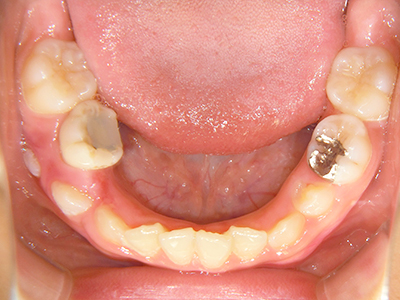

小児矯正について

歯並びの相談に来られるお子様は、口呼吸をしているケースが多く、これが歯並びに大きな影響を与えています。

ないき歯科クリニックでは、上あごの成長不足を補い、鼻呼吸を獲得しつつ歯列を整え、将来のお口をより健康な状態にすることをゴールに定める矯正治療をおこなっています。